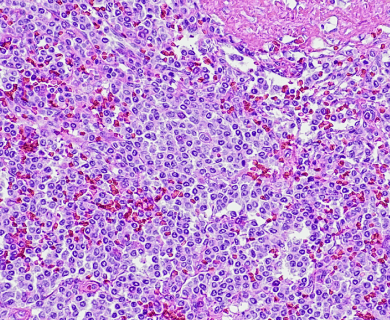

Pathologists look at tumor and tissue samples and determine what cells they can see. If the majority of cells from your mesothelioma sample are epithelioid cells, your mesothelioma subtype is determined to be epithelioid mesothelioma.

A tissue biopsy is the only way to diagnose epithelioid mesothelioma. This procedure involves taking samples of suspicious tissue. Pathologists examine the tissue samples under a microscope to identify specific cell characteristics.

Epithelioid mesothelioma cells clump together in groups and don’t tend to travel. These cell types are less likely to spread to other areas of the body. When a pathologist confirms the presence of specific cancer cells, an accurate diagnosis of your mesothelioma type can be made.

Epithelial subtype mesothelioma describes the type of cells the pathologist is seeing under the microscope when they look at a patient’s tumor.

While epithelioid is a subtype of mesothelioma, there are further subtypes of the epithelioid type. Pathologists can identify these cell subtypes with immunohistochemistry.